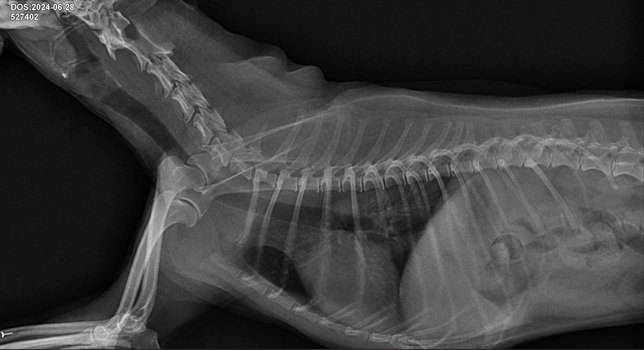

- 반려동물 건강반려동물Q. 기관지협착인가요 기관협착인가요? 아니면 둘다 있나요? 기관지염이 있나요? 기관염이 있나요?질문1. 기관지협착인가요 기관협착인가요? 아니면 둘다 있나요?질문2. 기관지염이 있나요? 기관염이 있나요?질문3. 사진 좌측상단에 날짜부분에 굉장히 좁아보이는데 이부분이 후두인가요? 후두가 부어있는건가요?질문4. 약간의 기도협착이 있나요?질문5. 협착과 염 상태가 어느정도인지 상중하로 알려주시면 감사하겠습니다